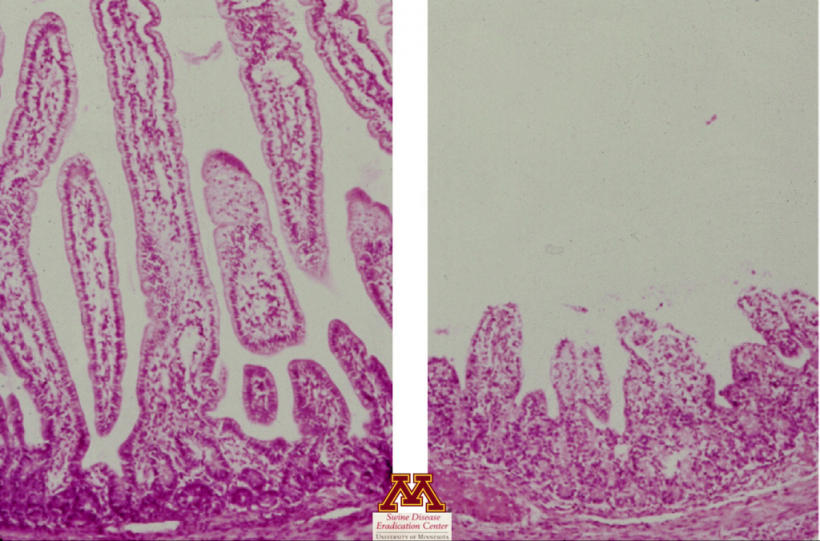

Atrofia das vilosidades causada por rotavírus. Foto de Swine Diseases por Perle Zhitnitskiy, DVM, MSpVM. Fonte: Dr. Carlos Pijoan https://creativecommons.org/licenses/by-nc/4.0/

- Avalia a presença de lesões tecidulares (atrofia das vilosidades no intestino delgado) que podem sugerir fortemente a presença de doença.

- Confirma a atrofia das vilosidades sugestiva de enterite viral.